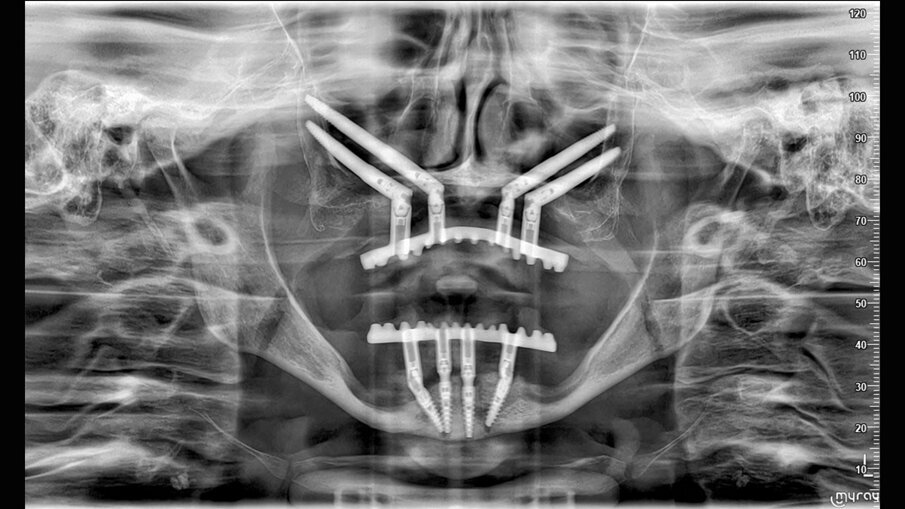

È presentata una riabilitazione con 4 impianti zigomatici (QUAD) in paziente con grave atrofia del mascellare. In questo caso la protesi con carico funzionale è stata consegnata alla paziente dopo 72 ore. Nelle immagini 1-4 viene mostrata la stereolitografia e la TC della paziente, mentre nelle immagini 5-7 viene mostrata la situazione iniziale e finale della paziente.

È stato applicato il protocollo ZAPA Zygomatic Anatomical Prosthetic Approach che definisce una successione di sequenze operative, convalidate da oltre 10 anni di chirurgia zigomatica, muovendo da un approccio protesico della riabilitazione:

- inserimento, affossamento e orientamento dell’impianto in funzione del progetto protesico (Figg. 8, 9);

- misurazione dell’altezza e angolazione del moncone con apposito strumento (Fig. 9);

- inserimento dei monconi protesici nei 4 impianti collocati – 2 standard e 2 zigomatici – e controllo della loro congruità mediante mascherina chirurgica (Figg. 10, 11).

- panoramica di controllo postoperatorio (Fig. 12);